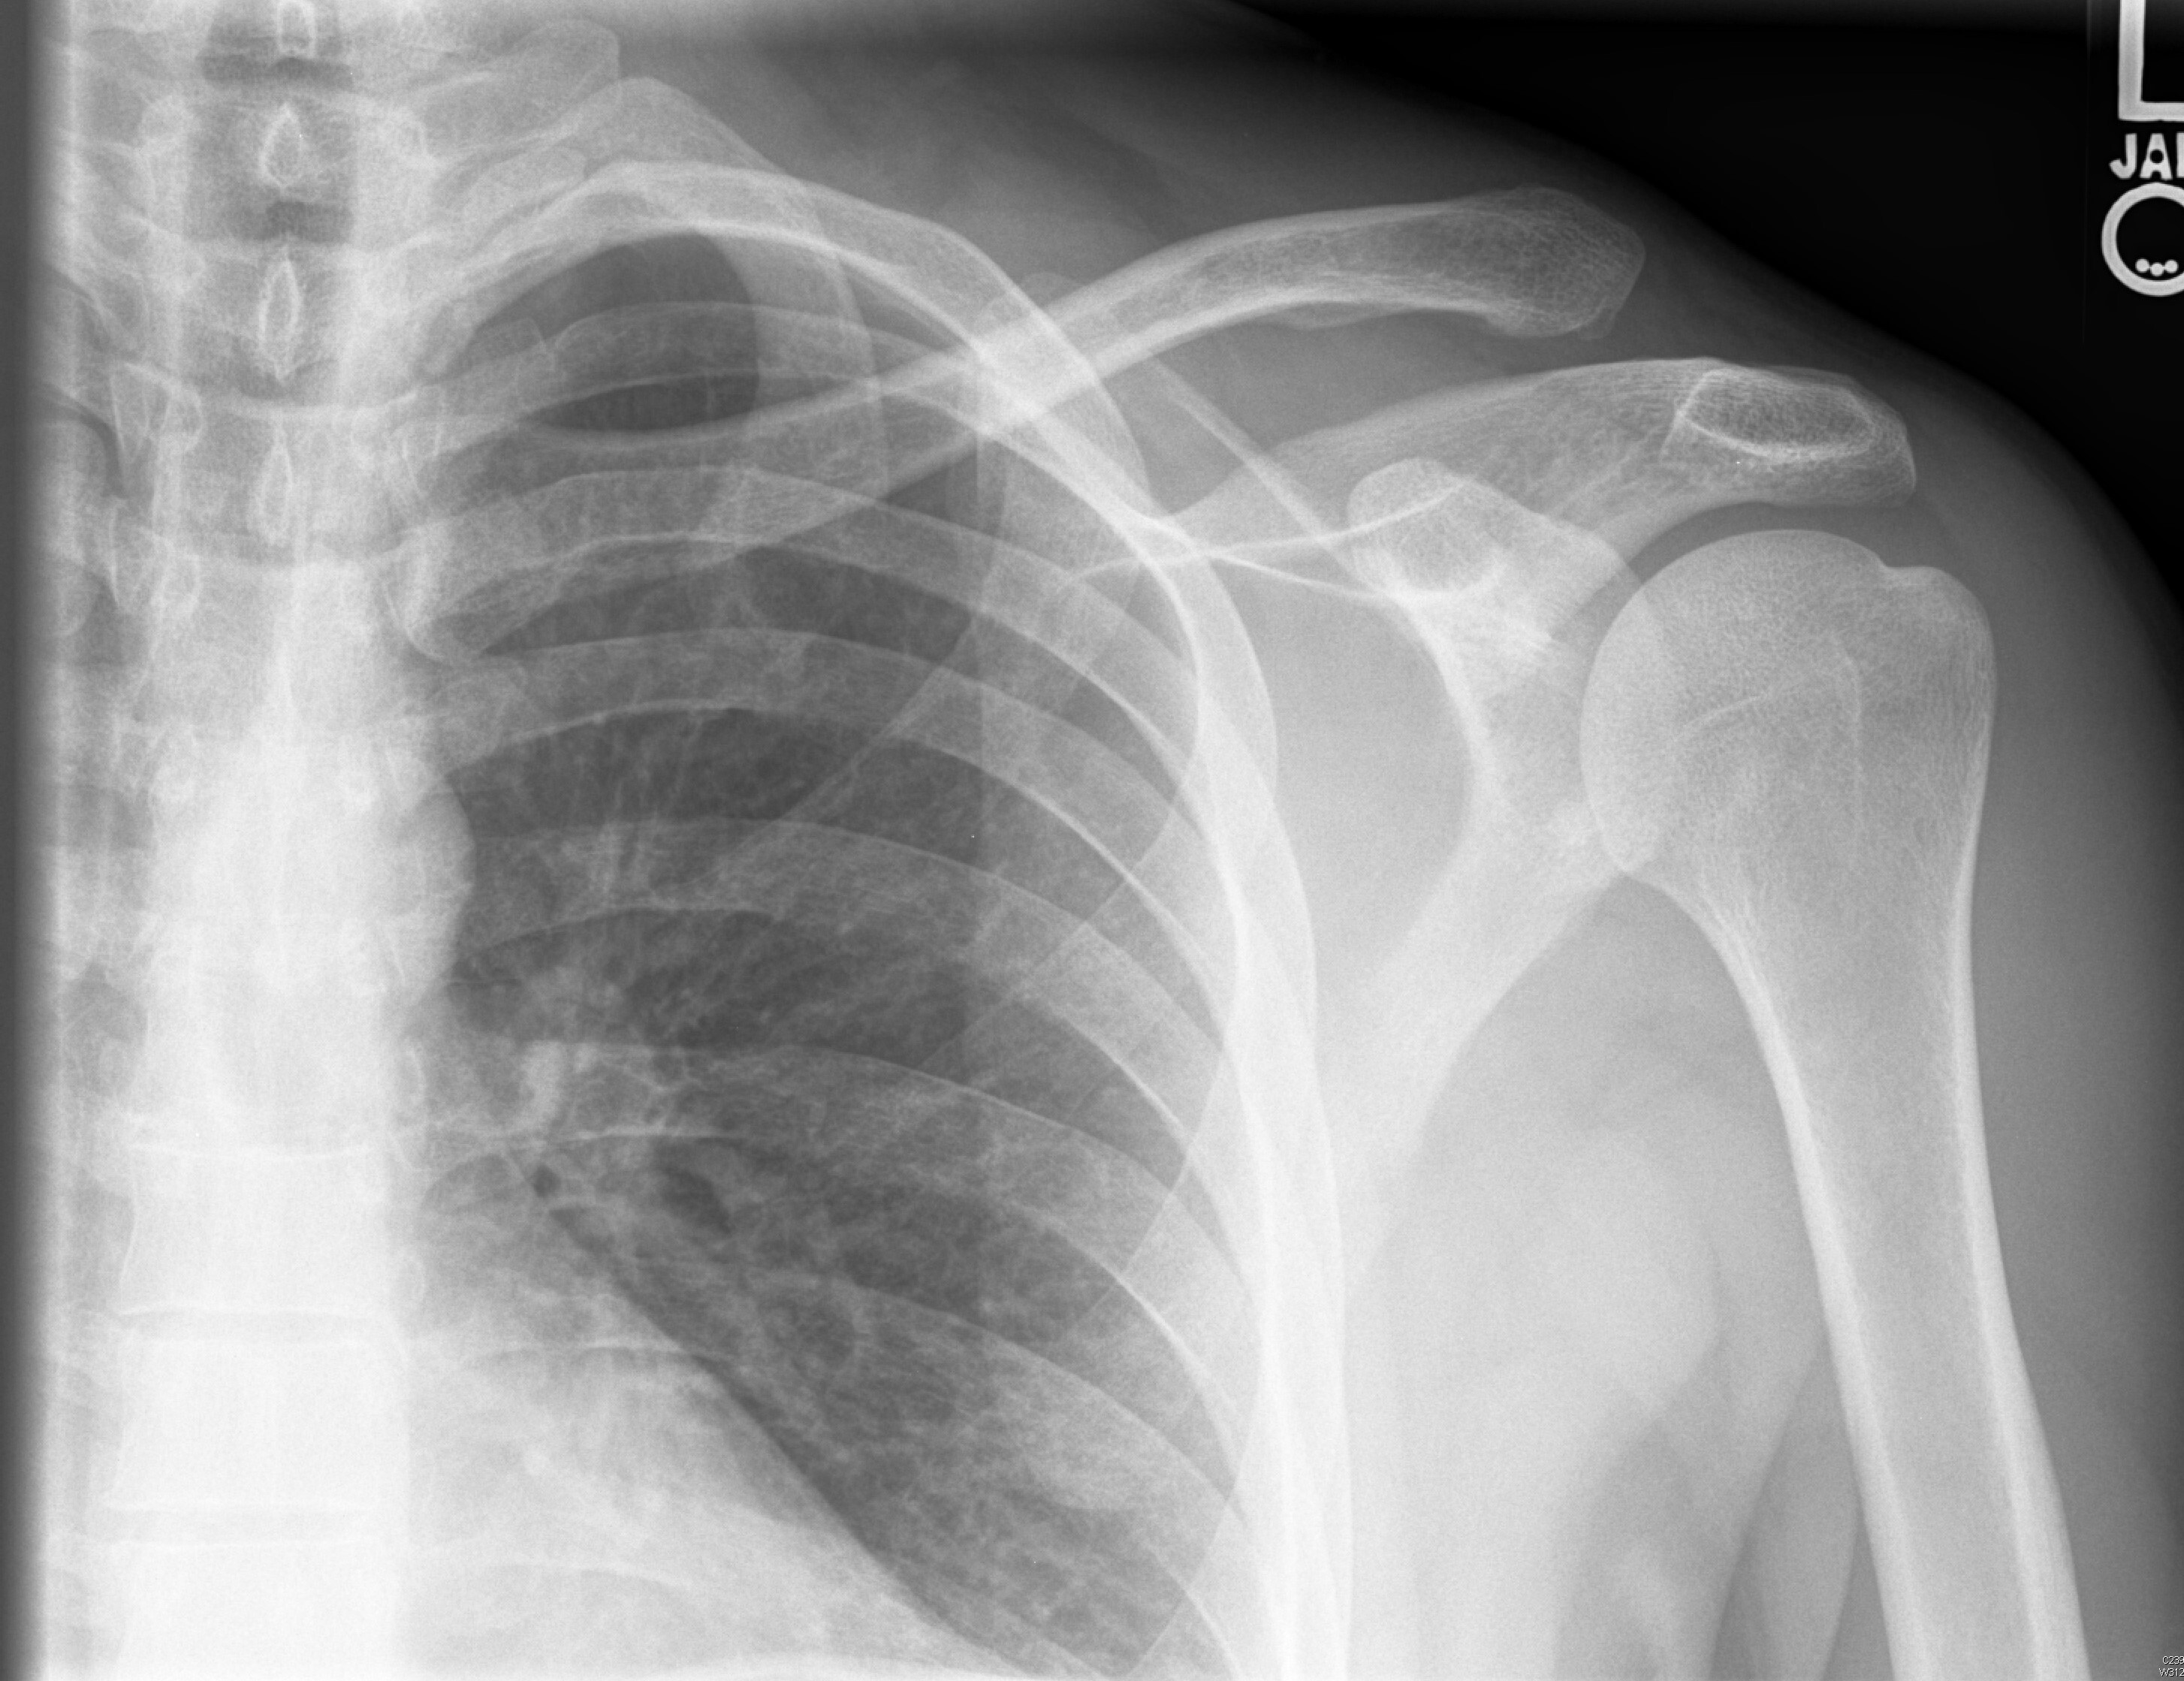

Standard radiographs are the imaging of choice, including AP, lateral, and Zanca (AP view performed by tilting the beam 10-15 degrees cranial) views. (See Figure 1.) Weighted stress views also may be considered to help evaluate the degree of displacement.37

Figure 1. Left AC Separation |

![]() |

AC: acromioclavicular Source: Used with permission from J. Stephan Stapczynski, MD. |